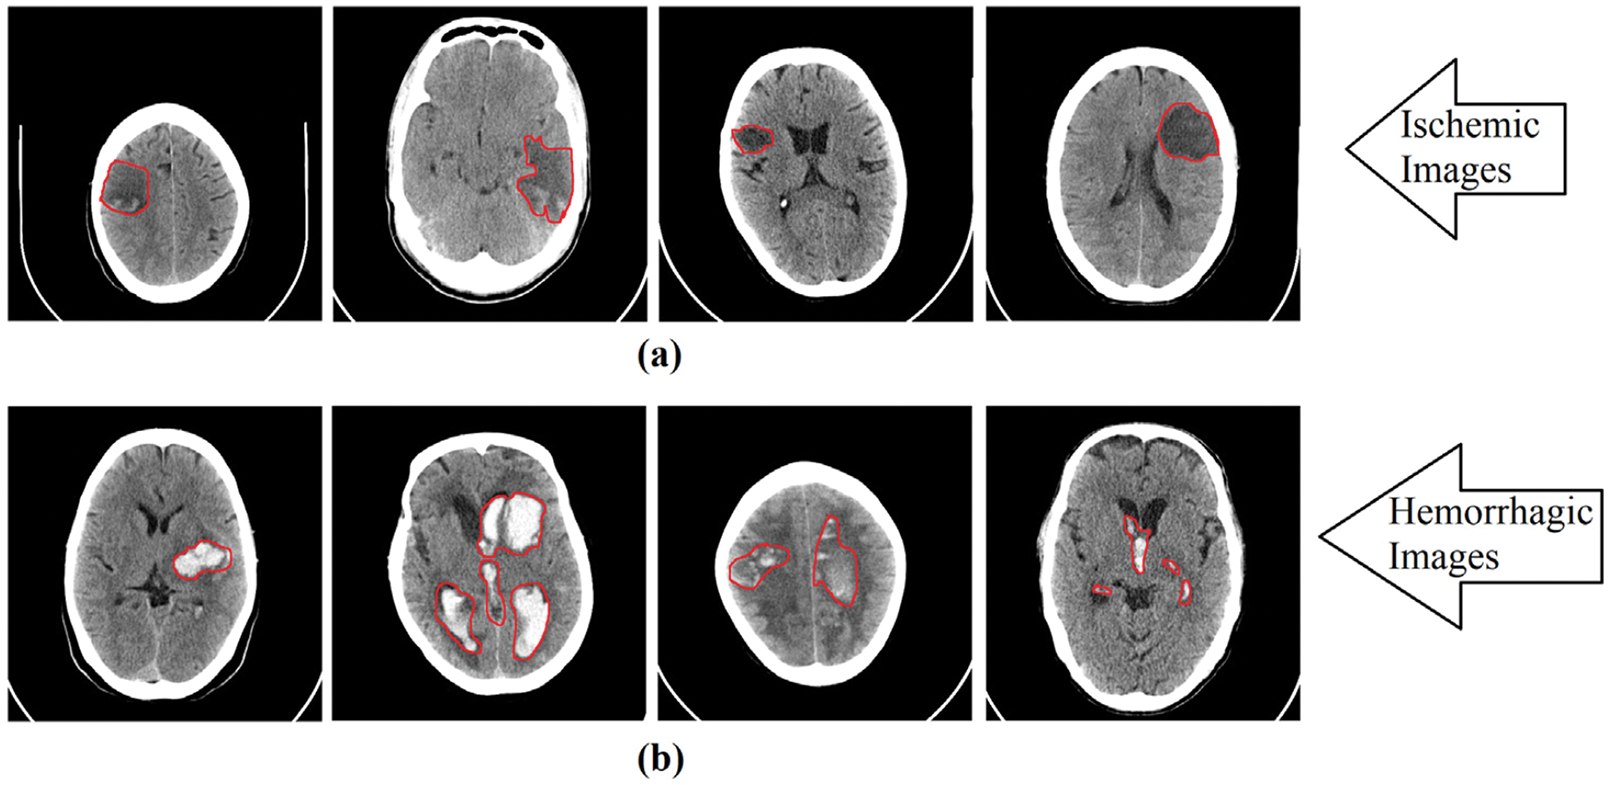

Fig. 2 shows the foci of ischemic and hemorrhagic stroke that were identified by medical professionals. The areas in the brain where the strokes occurred are indicated in purple in Fig. 2. The aim of our study is to develop a computer diagnostic system based on the CNN model for automated classification of cerebral strokes.

Figure 2: Red area marks the location of ischemic and hemorrhagic lesions on the images